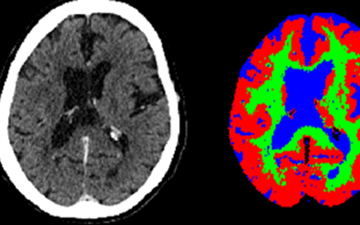

Científicos de la Universidad Politécnica de Madrid, junto con varios centros colaboradores, han conseguido convertir simples escáneres de tomografía computarizada (TAC) en imágenes tan potentes como las de una resonancia magnética, utilizando inteligencia artificial. Este logro abre nuevas vías para investigar la enfermedad de Alzheimer en personas con síndrome de Down.